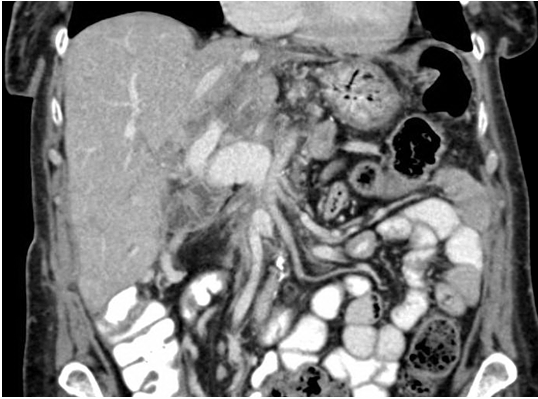

Final pathology confirmed a poorly differentiated adenocarcinoma in the head of the pancreas which was 35 mm in diameter, extending to the anterior border. Tumor was found invading the wall of the SMV. 2/26 lymph nodes were involved. The pathological staging was pT3, pN1, Mx. The margin was negative and there was no evidence of residual microscopic disease. The patient had an uneventful recovery and proceeded to have adjuvant chemotherapy. Repeat imaging at third and sixth months post-surgery revealed no evidence of recurrent disease. Furthermore, postoperative imaging revealed patent flow through her anastomosis, with no functional limitation regarding the potential for angulation at the junction of the SV and SMV with this turndown technique (Figure 5). The patient remained alive 42 months post-resection.

Cursor on image to zoom/Click text to open image

Figure 5: Computed tomography scan after three months post total pancreatectomy and splenic turndown reconstruction demonstrating patent flow through portal vein and ileal and jejunal tributaries.